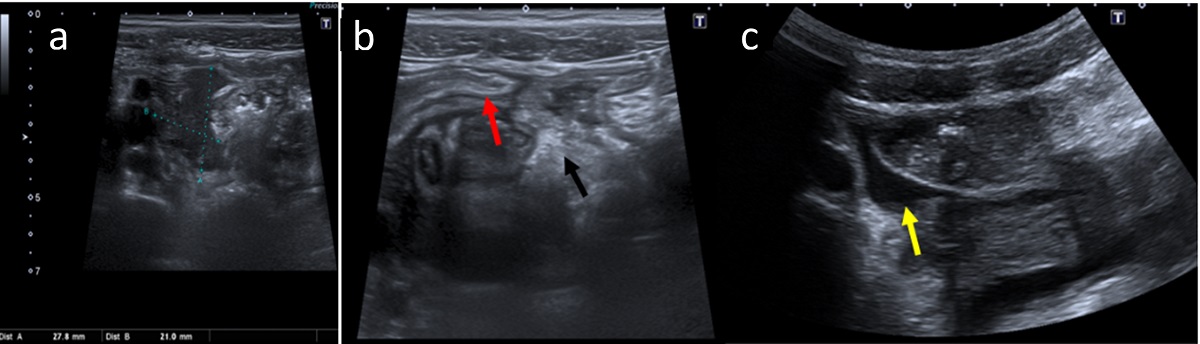

| Figura 2. Hallazgos ecográficos compatibles con apendicitis del muñón complicada: (a) colección adyacente al muñón apendicular de ecogenicidad heterogénea; (b) cambios inflamatorios locorregionales visualizados como un aumento de la ecogenicidad de la grasa periapendicular (flecha negra) y engrosamiento parietal del íleon terminal (flecha roja); (c) pequeña cantidad de líquido libre anecoico entre asas (flecha amarilla). |

|---|